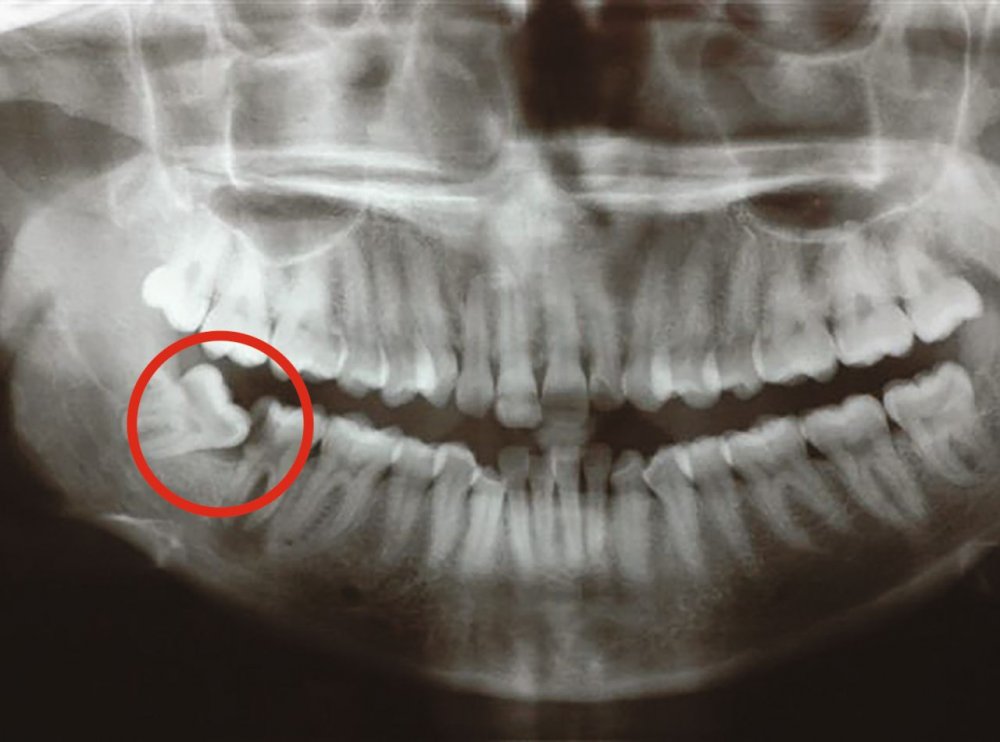

Normal halda insanın diş sırasında hər çənədə iki ədəd olmaqla, ümumilikdə dörd agıl dişi mövcuddur. Ağıl dişinin çıxması bəzi şəxslərdə heç bir kliniki əlamət və ya şikayətə səbəb olmasa da, bir çox hallarda müəyyən kliniki əlamətlərlə öyünü biruzə verir. Bu əlamətlər əsasən çənənin arxa tərəfində təzyiq, çənəni açıb baglama əsnasında agrı və məhdudlaşma kimi özünü göstərə bilir. Bu hallarda mütəxəssis konsultasiyasının önəmi olduqca böyükdür. Belə ki müayinə zamanı cərrah-stomatoloq kliniki və radioloji dəyərləndirmə apararaq dişin dogru pozisiyada yerləşib yerləşmədiyi, dişləmə çıxma ehtimalını, agıl dişinin çənəyə görə ölçüsü və çənə darlıgı kimi durumları dəyərləndirərək tətbiq edilməli olan müalicə taktikasını müəyyən edir.

- Retensiyon ağıl dişinin spontan və ya ortodontik olaraq dişləmə çıxma ehtimalı mövcud deyilsə

- Ağıl dişində ikincili yerləşmə deformasiyası varsa və bunun müalicəsi mümkün və ya tövsiyyəolunan deyilsə

- Ağıl dişi qonşu dişdə karies, sorulma, parodontal problemlər və s. yaradırsa